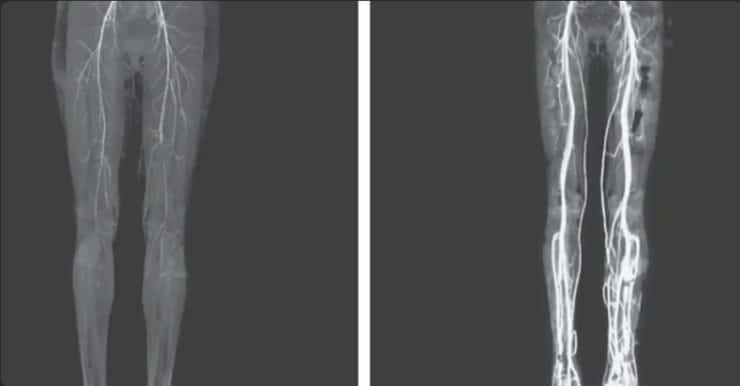

Further examination revealed that no pulse could be detected in her popliteal and dorsalis pedis arteries, suggesting severe circulation issues. A CT scan confirmed that her arteries had significantly narrowed.